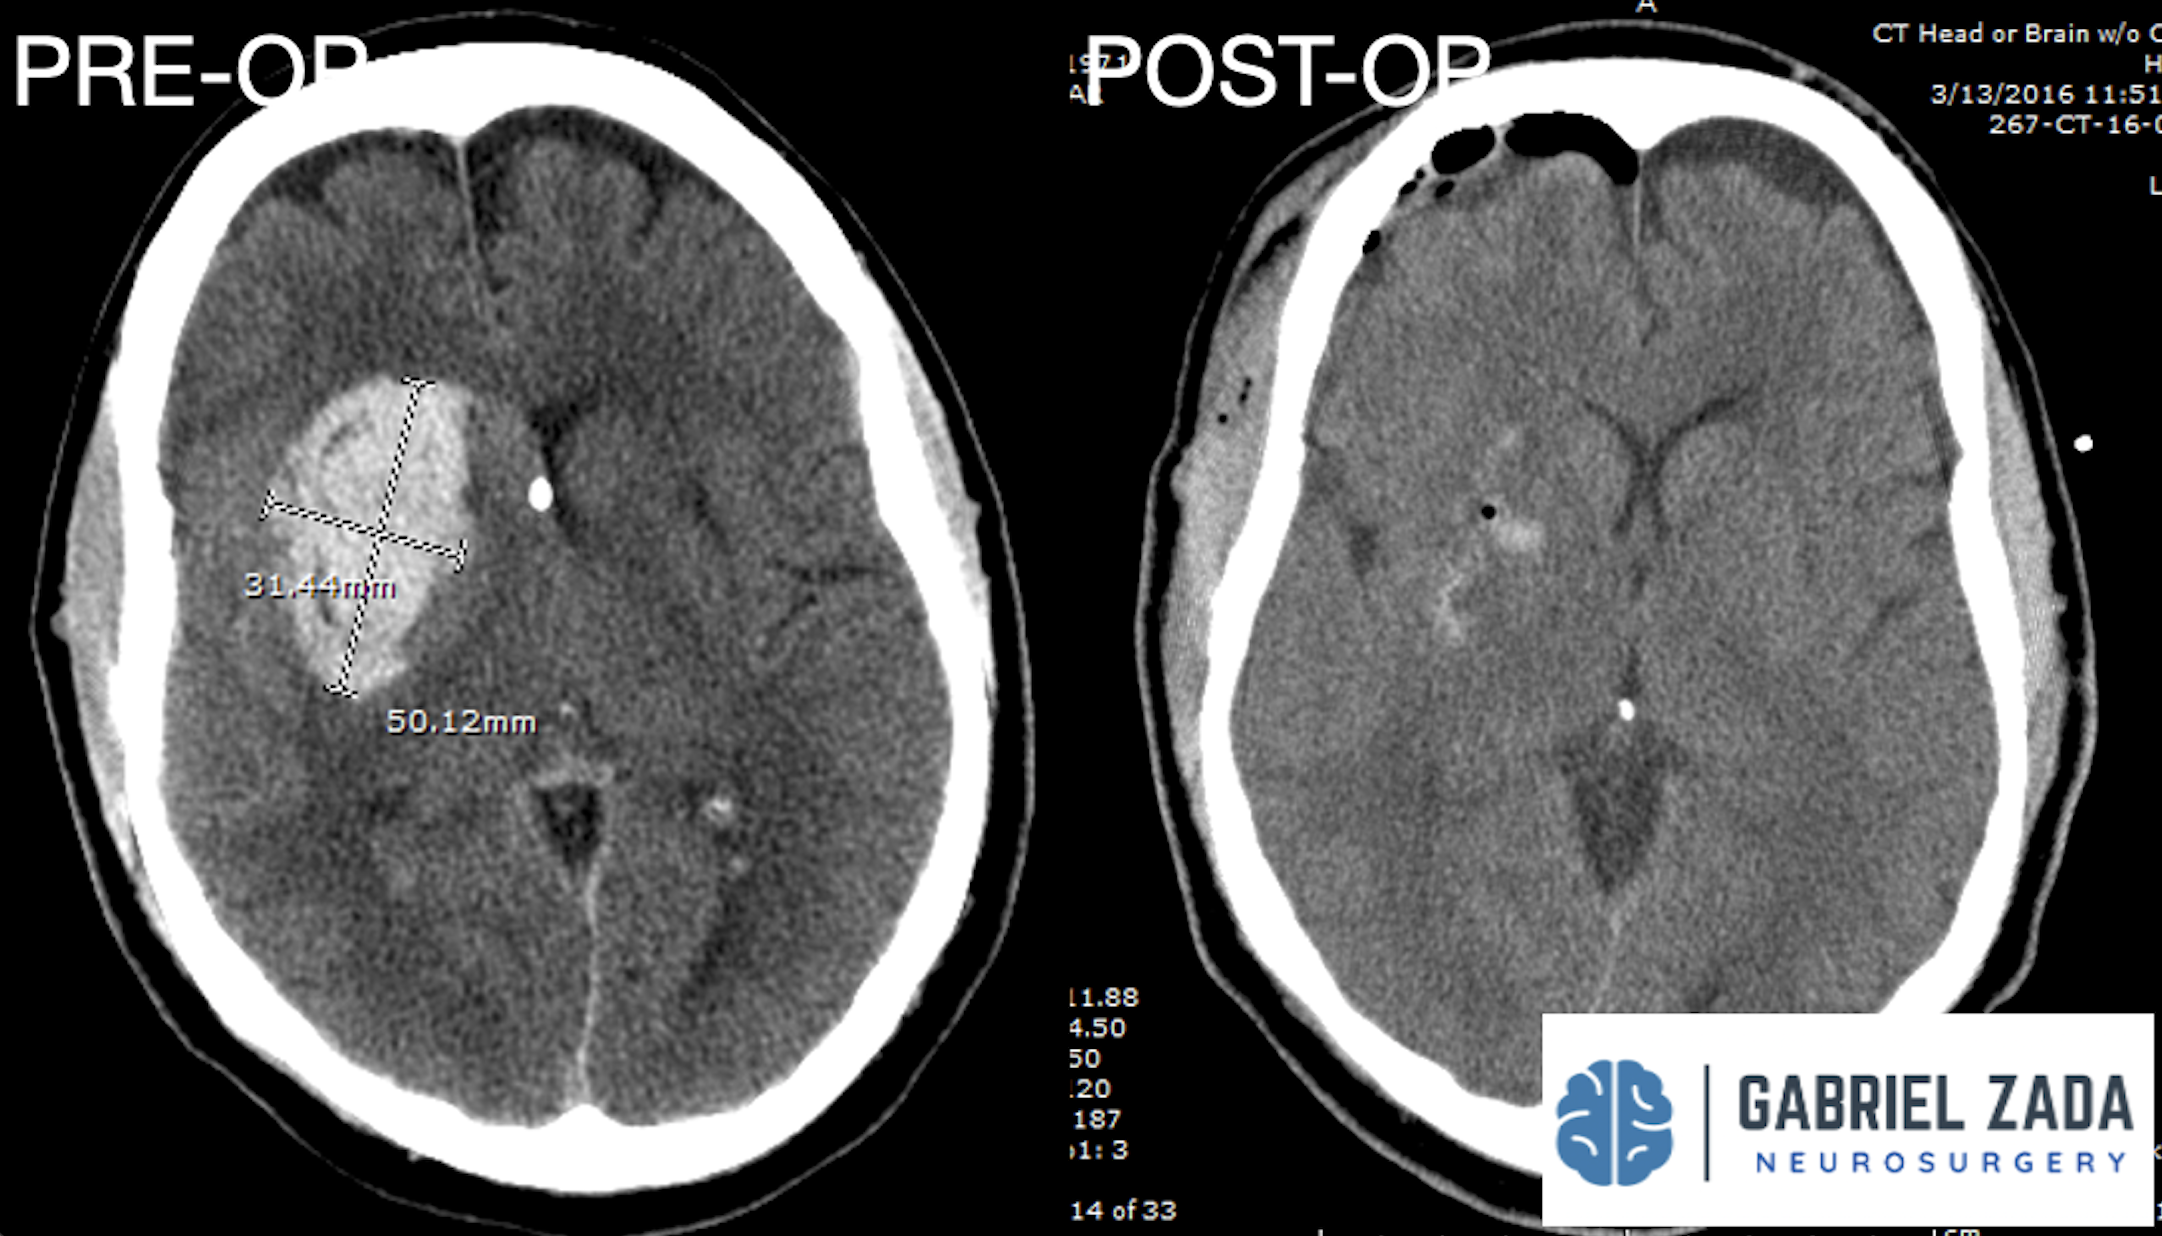

Explore this comprehensive gallery featuring pre‑ and post‑operative imaging of patients with skull‑base tumors treated by Gabriel Zada, MD, MS, FAANS, FACS. These cases highlight Dr. Zada’s expertise in advanced neurosurgical techniques and outcomes.

*Representative cases shown for educational purposes. All images de-identified. Individual results vary.